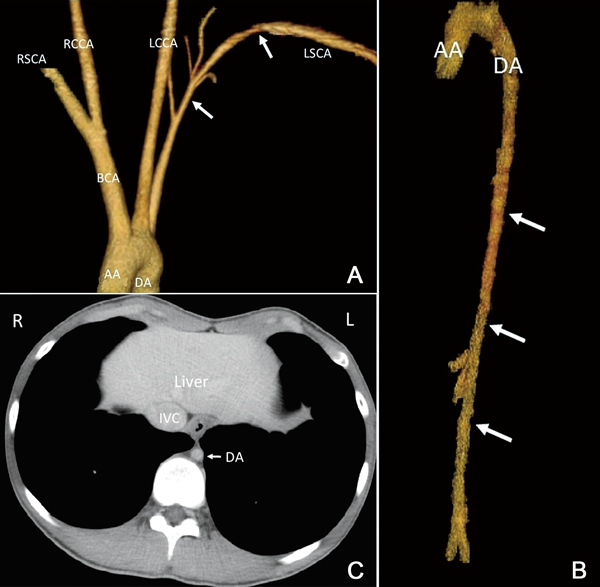

Stenoses in the Left Subclavian Artery and Descending Aorta in a Patient with Williams Syndrome